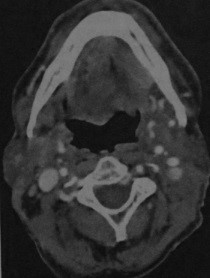

- Асимметричное образование, расположенное на дне ротовой полости

- Плотность идентична или несколько превышает плотность мышц

- Умеренное усиление после введения контраста

- Крупные опухоли могут содержать участки некроза и вызывать деструкцию кости

- Поражение поднижнечелюстных и яремно-двубрюшных лимфатических узлов на стороне опухоли

- Артефакты (зубные) можно свести к минимуму при исследовании под разными углами.

Рак дна полости рта, опухоль расположена около нижней поверхности языка слева. КТ с контрастированием. Заполненная альвеолярно-язычная борозда имеет повышенную плотность относительно противоположной стороны.